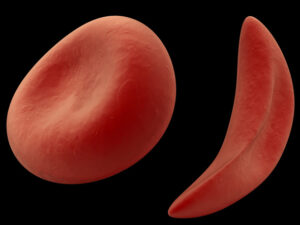

Quando gli animali vanno in letargo, anche il loro cervello va incontro ad una serie di modificazioni per affrontare il freddo e il lungo “sonno”. Al loro risveglio, con il ritorno alle temperature corporee fisiologiche, il ripristino delle normali attività cerebrali avviene anche grazie ad una proteina, RMB3, che è fondamentale per prevenire la perdita di connessioni neurali alle basse temperature e per favorirne lo sviluppo di nuove in primavera.

L’ESPERIMENTO. Nello studio, finanziato dal Medical Research Council e pubblicato su Nature, i ricercatori hanno osservato gli effetti del letargo sui due gruppi di topi, sani e con malattia di Alzheimer.Dopo 45 minuti di ipotermia a 16-18 gradi, al ripristino della temperatura fisiologica, la proteina è entrata in funzione nei soli topi sani e non nei malati, con conseguente mancato ripristino delle sinapsi al “risveglio”. Inoltre, la degenerazione dei neuroni tipica della malattia appare più accelerata tanto più basso il livello di RMB3.